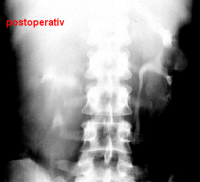

Die Nierenfreilegung und Abszessdrainage bzw. der postoperative Krankheitsverlauf im obigen Fall (s. Abbildung 6) sind in den Abbildungen dargestellt (Abbildung 9,10).